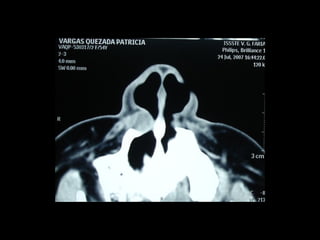

Imagen microscópica de osteitis, inicialmente existe una etapa de

osteoclastosis seguida por regeneración. No siempre el hueso

regenera en su totalidad y sigue el curso de cualquier inflamación

dejando un area de tejido fibroso que con el tiempo puede

calcificarse (hueso denso)

Manejo con antibióticos obligado

Revisión periódica